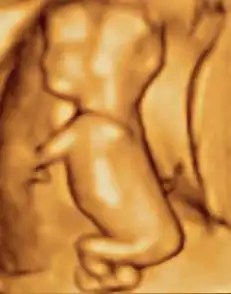

A dating scan at 12 weeks

Obstetric ultrasonography is routinely used for dating the gestational age of a pregnancy from the size of the fetus, determine the number of fetuses and placentae, evaluate for an ectopic pregnancy and first trimester bleeding, the most accurate dating being in first trimester before the growth of the foetus has been significantly influenced by other factors.[22] Ultrasound is also used for detecting congenital anomalies (or other foetal anomalies) and determining the biophysical profiles (BPP), which are generally easier to detect in the second trimester when the foetal structures are larger and more developed.[23]

X-rays and computerized tomography (CT) are not used, especially in the first trimester, due to the ionizing radiation, which has teratogenic effects on the foetus.[24] No effects of magnetic resonance imaging (MRI) on the foetus have been demonstrated,[25] but this technique is too expensive for routine observation. Instead, obstetric ultrasonography is the imaging method of choice in the first trimester and throughout the pregnancy, because it emits no radiation, is portable, and allows for realtime imaging.[26]

The safety of frequent ultrasound scanning has not been confirmed. Despite this, increasing numbers of women are choosing to have additional scans for no medical purpose, such as gender scans, 3D and 4D scans.[27] A normal gestation would reveal a gestational sac, yolk sac, and fetal pole.[28]

The gestational age can be assessed by evaluating the mean gestational sac diameter (MGD) before week 6, and the crown-rump length after week 6. Multiple gestation is evaluated by the number of placentae and amniotic sacs present.[29]